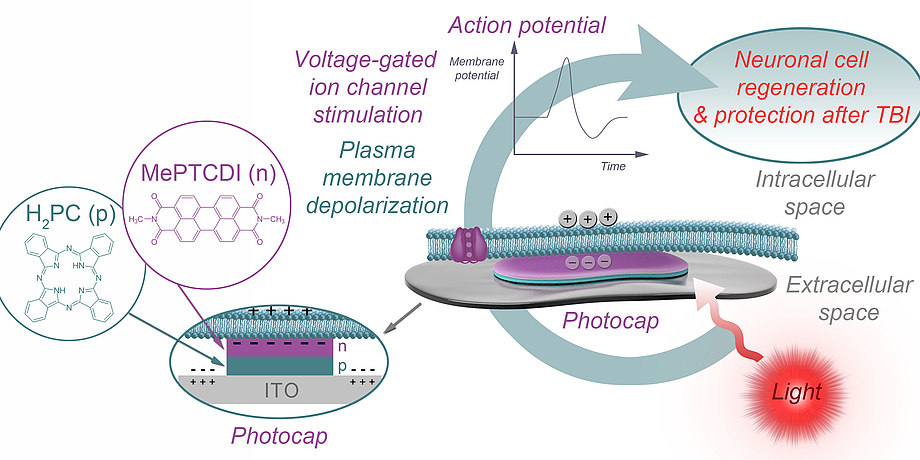

Organic pigment photocapacitors

The basic idea behind stimulation using photocaps is shown in Figure 1. The attached part of the cell membrane is separated from the top layer of the photocap by a thin layer of electrolyte, and the free part is in contact with the bath. Upon illumination, the top-layer of the photocap becomes negatively charged, resulting in localised displacement currents across the photocap/electrolyte interface and a profile of extracellular voltage in the area of cell adhesion. As a consequence, the attached plasma membrane is depolarised and voltage-gated ion channels are activated, triggering cellular action potentials. The photocaps recently developed by an international partner of the LOGOS-TBI team (Glowacki et al., Linköping University) are easy to produce, stable and non-toxic, and enable electrical stimulation of neurons with safe light intensities, without the need for external wiring. They can be produced in thicknesses three orders of magnitude lower than their silicon-based counterparts. Taken together, these features make photocaps the ideal candidate when it comes to studying mitigation of injuryinduced deficits in neural communication by means of neuronal stimulation.